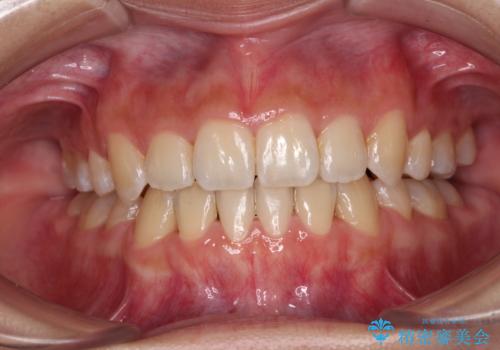

すきっ歯をインビザラインできれいな歯並びに改善

- 前歯の隙間を気にして来院された患者様です。

隙間や叢生の程度はそれほど著しいものではなかったので、インビザラインでもワイヤー矯正でも対応可能でしたが、極力目立たない装置を希望されたため、インビザラインにて矯正治療を行うこととしました。

すきっ歯の原因は色々ありますが、嚥下や発音時の舌突出癖が大きな原因となることがあります。

こちらの患者様も強い突出癖があったため、舌のトレーニング指導を行いました。